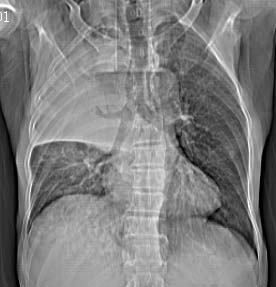

病人女 60岁 咳嗽 气促十余天,大叶性肺炎.

右肺上下叶均见 大片状密度增高影,边界清晰,其内可见支气管充气征,气管支气管通畅。纵膈略向右移位,其内无肿大淋巴结影。首先考虑炎性病变。不排除一些特异性的炎症。不知道发烧吗??wbc高吗??建议治疗后复查!!

看影响还是首先考虑炎性改变,建议实验室检查,还有要警惕炎性肺泡癌,具有的枯枝征象。

右肺感染性病变(大叶性肺炎可能);建议抗炎治疗后复查。

看影像还是首先考虑炎性改变,建议实验室检查,还有要警惕炎性肺泡癌,具有的枯枝征象